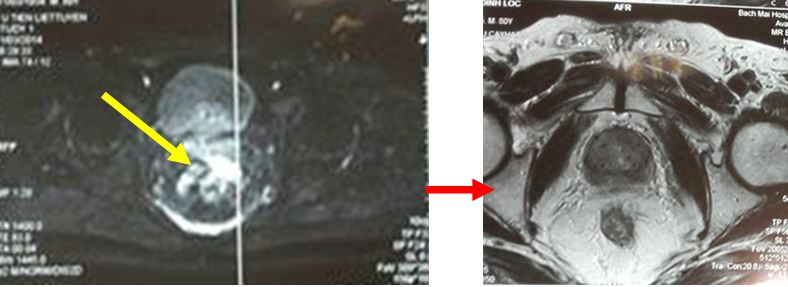

Sau điều trị 7 tháng (12/2015):

• Bệnh nhân thể trạng tốt, đi tiểu bình thường, tiểu tiện tự chủ, không đi ngoài ra máu.

• Chụp MRI: Không thấy khối bất thường trên hình ảnh MRI tiểu khung

• Xét nghiệm PSA toàn phần tiếp tục giảm xuống rất thấp còn 0,26 ng/ml, PSA tự do 0,01 ng/ml.

So sánh trước và sau điều trị:

Trước điều trị: tiểu són, tiểu nhiều lần; trên cộng hưởng từ khối u kích thước 12 x 15 mm, ranh giới không rõ, chưa xâm lấn vỏ bao và túi tinh; PSA = 2,4 ng/ml

Sau điều trị 7 tháng: thể trạng tốt, đi tiểu bình thường; trên hình ảnh cộng hưởng từ không có khối bất thường; PSA giảm xuống còn 0,26 ng/ml